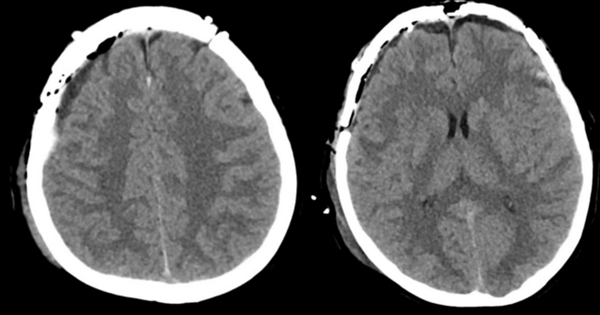

6小时后,再次复查CT显示,双侧硬膜外血肿较前明显增多。如不及时干预,血肿将迅速压迫脑组织,可能导致昏迷、脑疝等风险,甚至危及生命。

▲术前复查头颅CT,提示伴双侧部硬膜外血肿较前明显增多。

▲术后CT显示颅内血肿清除彻底,恢复情况良好。